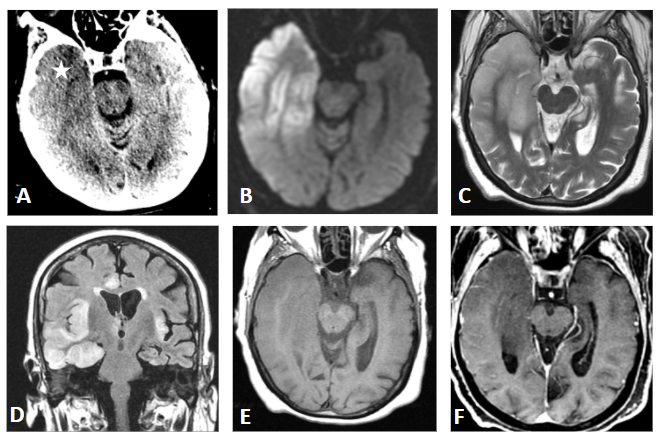

Figura A. TC  craneal sin contraste: Hipodensidad en región temporal medial derecha (asterisco) sin distribución en un territorio arterial.

Figura B. RM cerebral DWI: Restricción corticosubcortical en difusión (b=1000).

Figura C. RM cerebral T2-axial:  Se aprecia una tumefacción e hiperintensidad corticosubcortical del lóbulo temporal derecho.

Figura D. RM cerebral FLAIR-coronal: Afectación bilateral asimétrica temporal, ínsulas y cíngulos.

Figura E. RM cerebral T1-axial: No signos de hemorragia.

Figura F. RM cerebral T1-axial con gadolinio: No captación de contraste.